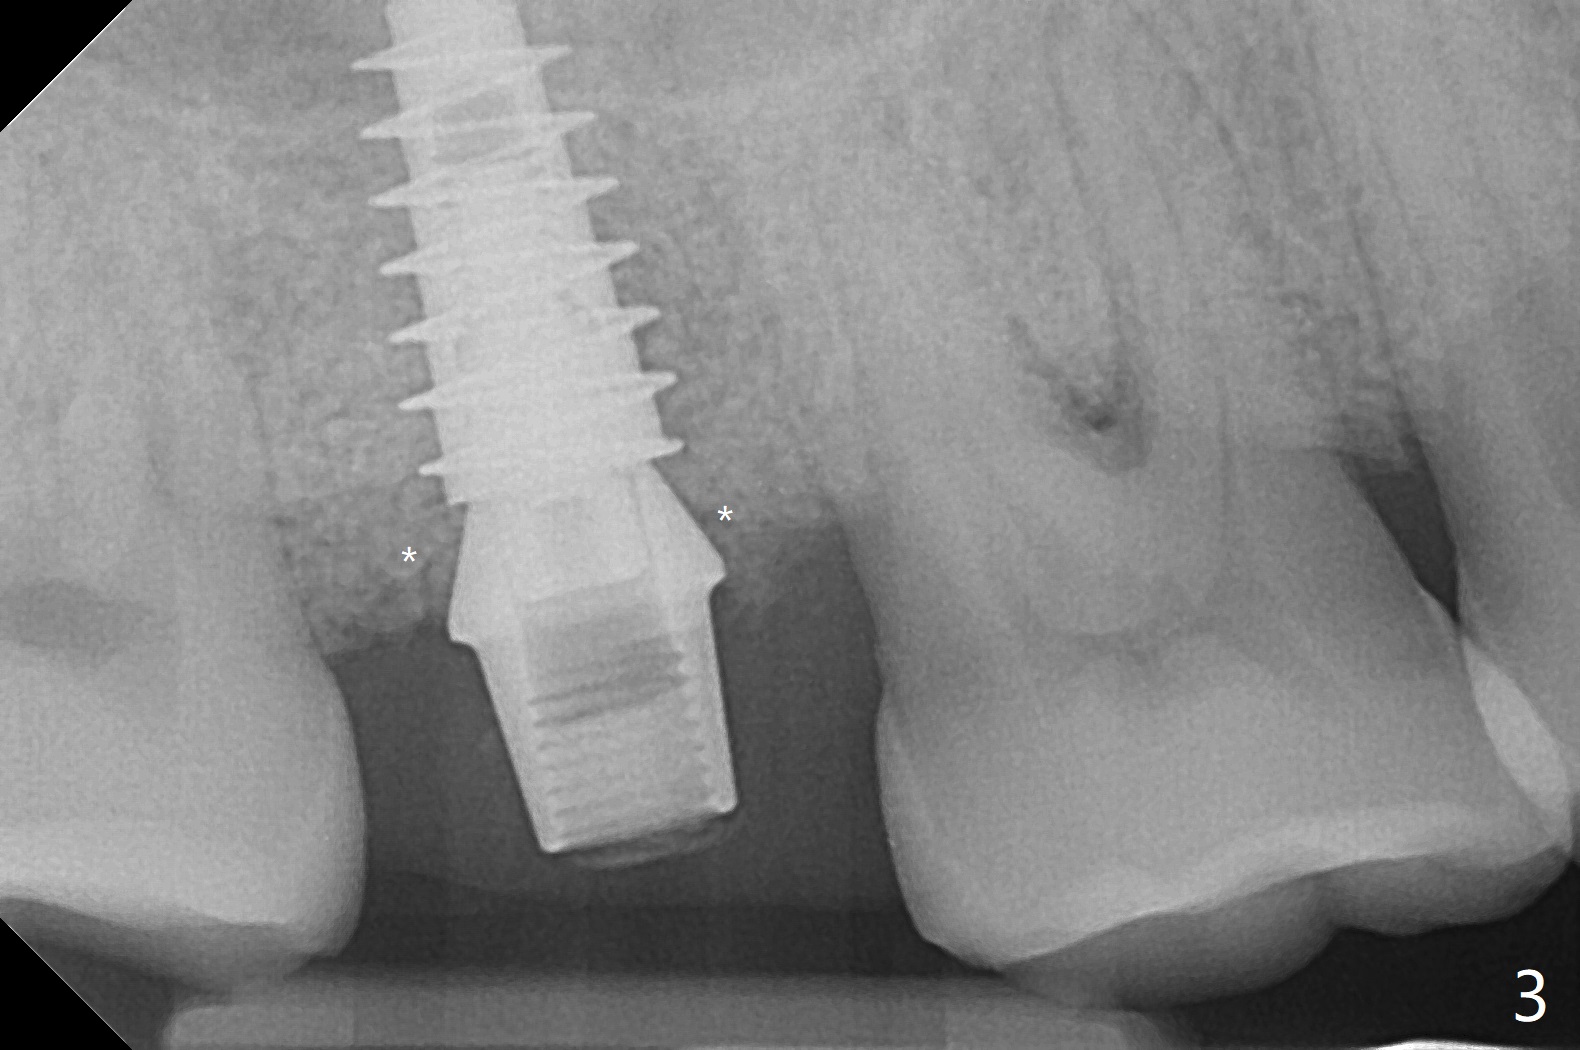

The tooth #2 has severe distobucal (DB) infection before and after extraction (Fig.1 *); sinus lift is done with 4.5x11 mm dummy implant using guide. After placing bone graft into the sinus and the osteotomy (Fig.2 black *), a 5x9 mm implant is placed with >30 Ncm. Second round of bone graft is placed around the implant, including DB defect (white *). Then a 5x4(2) mm pair abutment is placed, followed by the third round of bone graft (Fig.3 *). Finally an immediate provisional is fabricated to keep the graft in place. The implant is loose nearly 4 months postop.